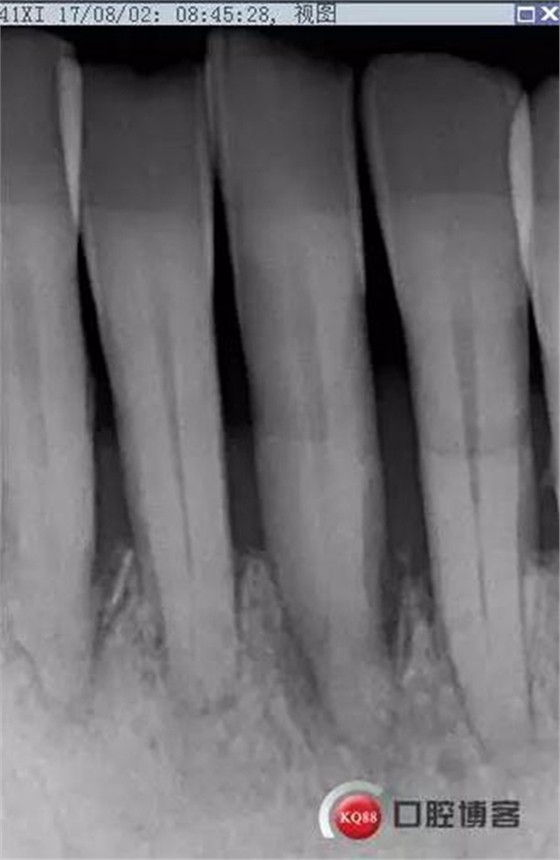

處理:上橡皮障,31開髓,測(cè)工作長(zhǎng)度17mm,含氯沖洗液沖洗,機(jī)擴(kuò)至04錐度30#,超聲蕩洗,一次性根充。33-43牙齒鄰接處super bond粘結(jié)固位,行松牙固定。調(diào)合。拍根充術(shù)后片,未達(dá)根尖,懷疑遺漏根管,去除根充物后,繼續(xù)探查根管,找到舌側(cè)根管,測(cè)長(zhǎng)度20mm,時(shí)間原因,未行擴(kuò)根,氫氧化鈣暫封。

當(dāng)日根充后思考:

圖省事,沒(méi)有拍術(shù)中試尖片,導(dǎo)致術(shù)后重新去除根充物,再次探查,耽誤時(shí)間。

想當(dāng)然的認(rèn)為31單管,忽略了尚有5-10%概率的雙根管情況。

事后再次查看術(shù)前片,可以看到兩個(gè)根管影像,忽略了。

處理:31去暫封,手用銼疏通根管,沖洗,機(jī)擴(kuò)至04錐度30#,超聲蕩洗,封維塔,拍片。

由于兩次根管內(nèi)封藥后,頰根處均有多余藥物擠出根尖孔,考慮根尖孔處受破壞或根尖周炎癥導(dǎo)致牙周膜疏松,故封藥兩周后復(fù)診。

2017-08-25

處理:31去暫封,疏通根管,沖洗,試尖,拍片,根充,拍片,恰填,根尖孔外無(wú)多余藥物滲出。樹脂充填開髓孔。33-43樹脂纖維帶固定,調(diào)合拋光。